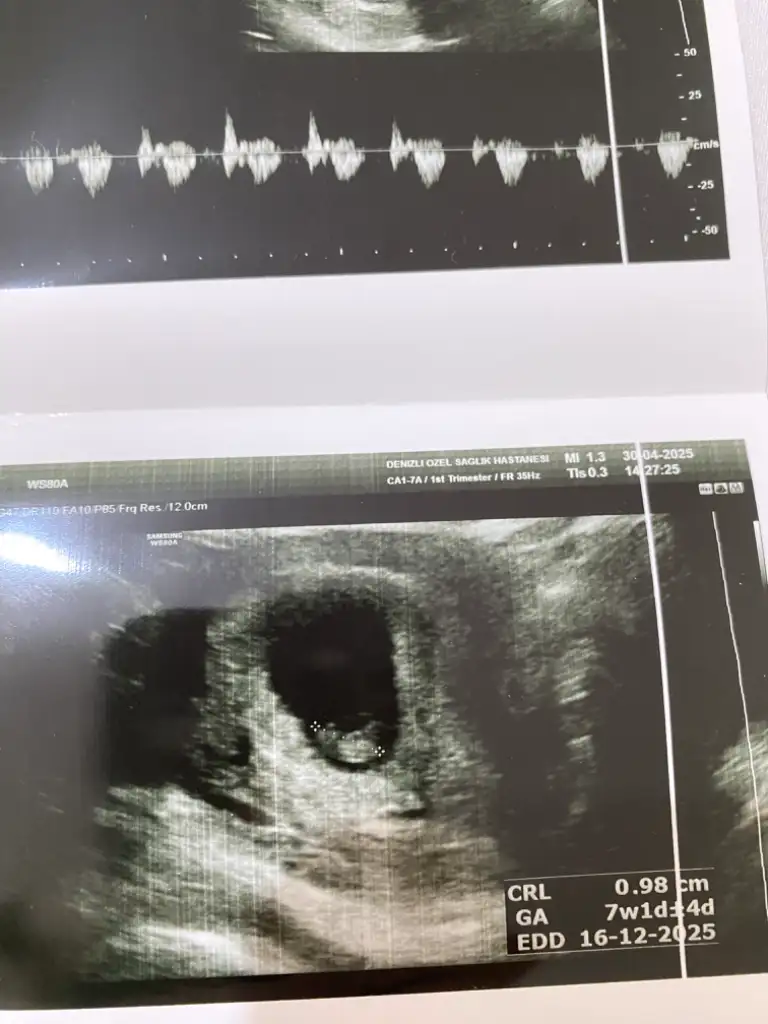

Yaa bizede bakabilir misiniz çok merak ediyorum görsellerde ilk görsel 10+4 diğer görseller 6+4 haftalık :)Pek iyi anlamıyorum ama nub teorisi fotolarına baktığım kadarıyla kız gibi görünüyor

Banada bakabilir miisniz görsel olarak yorumlara ekledim :) ilk görsel 10+4 diğer görseller 6+4 haftalıkken karından ultrasonla bakıldı

benimkine de bakın bu nedir iki bacak arası görünüyorVajinal ultrasonla bakıldıysa bebeğiniz kız olabilir